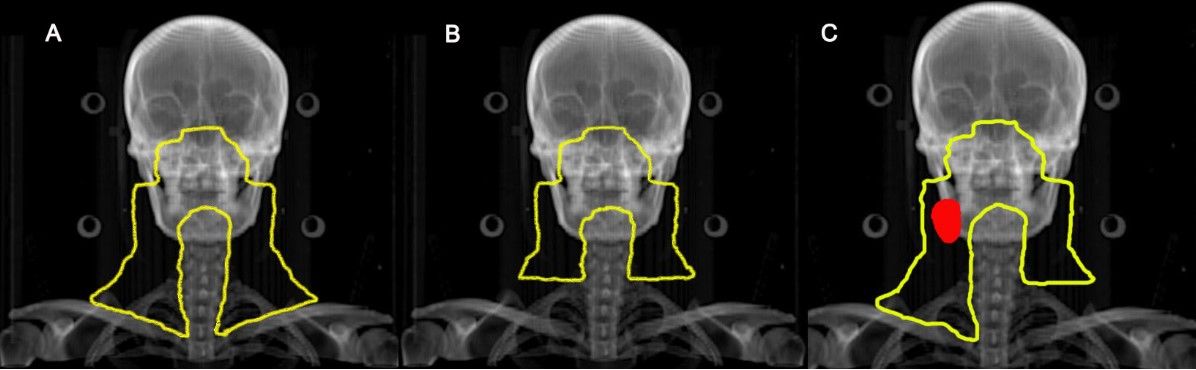

马骏、唐玲珑团队:更少照射范围让鼻咽癌患者获得更高生活质量